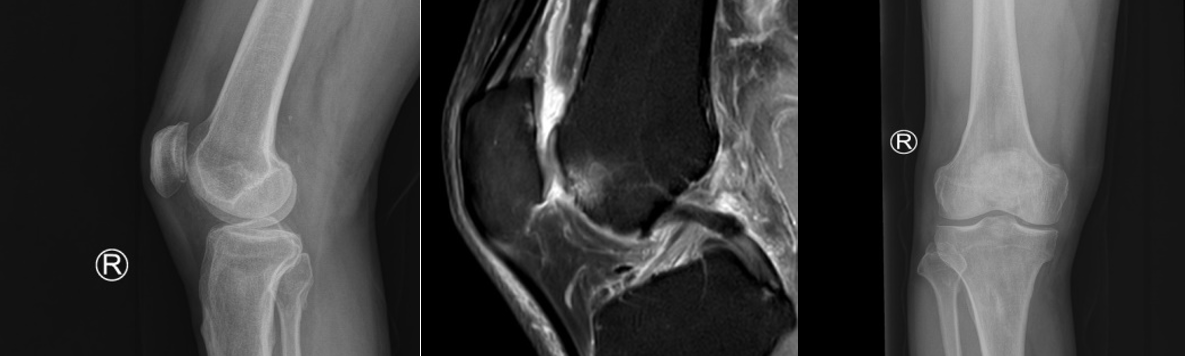

接诊后,膝关节外三科权松涛与主治医师王飞团队为王先生进行了系统而全面的检查。通过详细的体格检查和影像学评估,发现王先生的膝关节问题主要集中在髌股关节,其髌骨与股骨滑车之间的软骨已严重磨损,髌股关节间隙显著狭窄,但膝关节的内外侧间室尚且完好。这是一种典型的髌股关节炎,对于保守治疗无效的严重病例,创伤更小、恢复更快髌股关节置换术是能最大程度保留自身关节结构和功能的最佳治疗方案。